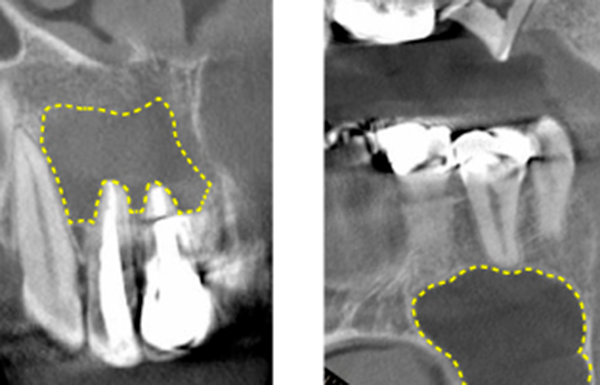

Bacteria that have reached the pulp will travel through the root canal, the cavity where the pulp used to be, to the the root apex, and finally proliferate in the bone that supports the tooth (Fig. 8).

This is called a "periapical lesion" (Fig. 9), and when this occurs, the tooth begins to move easily.

- Teeth with severely resorbed or fractured tooth-supporting bone(approximately 2/3 resorbed). (Figures 13 and 14)